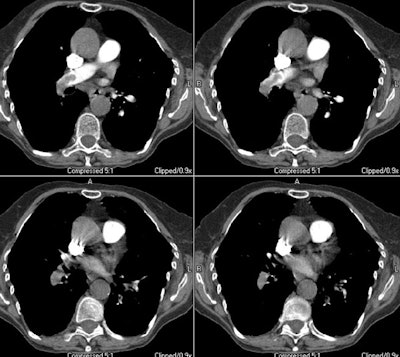

Case 8: Central PE with right heart strain.

The images below are from an elderly patient with a large embolic clot burden. There is a right main pulmonary artery embolism and the right descending pulmonary artery is completely obstructed (first image). The patient had multiple other emboli bilaterally. Note the right ventricular dilatation (in which the greatest short axis measurement of the right ventricular cavity is wider than the left ventricular cavity and the deviation of the interventricular septum toward the left ventricle (second image)- these findings are indicative of right heart strain and an increased mortality risk.